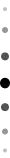

图片来自腾讯国际新闻

图片中,小琼斯的下巴短小,后缩严重, 14岁的她已不能通过矫正来刺激下颌骨的发育,结果就是她除了需要正常的正畸治疗来排齐牙齿,还需进行正颌治疗。